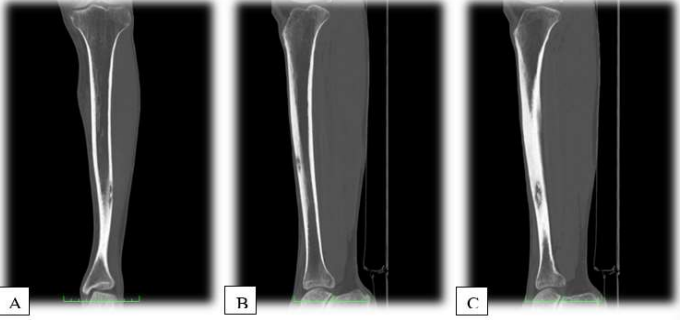

Radiographs taken in the ED demonstrated a lesion with subtle sclerosis in the anterolateral midshaft of the left tibia (Figure 1). A CT scan of the left leg revealed a focal cortical lesion with central calcification suggestive of an osteoid osteoma in the anterior aspect of the left mid-tibial shaft. Proximal to this lesion, another similar lesion with a periosteal reaction was noted just distal to the tibial tuberosity (Figures 2-4).

Figure 2: Preoperative Axial CT Scan of the Left Tibia. (A) This axial CT scan reveals a nidus characteristic of an osteoid osteoma in the cortex of the left tibia. The image shows a distinct round lucency with a surrounding sclerotic reaction. In addition, there was a central area of calcification. (B) Similar to the previous image, this axial CT scan further illustrates the cortical nidus associated with the osteoid osteoma. The lucent area is surrounded by reactive sclerosis, which is typical for this condition. (C) Another axial view highlighting the nidus and the surrounding sclerosis. The nidus appears as a small, well-defined radiolucent area within the thickened cortical bone

Figure 3: Preoperative Coronal CT Scan of the Left Tibia. (A) This coronal CT scan provides longitudinal view of the left tibia, clearly depicting the cortical thickening and the nidus of the osteoid osteoma, with a central calcification. The vertical extent of the lesion was well visualized. (B) A detailed sagittal view showing the vertical alignment of the lesion and the associated cortical reaction. The sclerotic area around the nidus is prominent, confirming the osteoid osteoma diagnosis. (C) Extended sagittal view further emphasizing the longitudinal spread of the osteoid osteoma lesions within the tibia. The surrounding bone sclerosis and cortical thickening are clearly evident